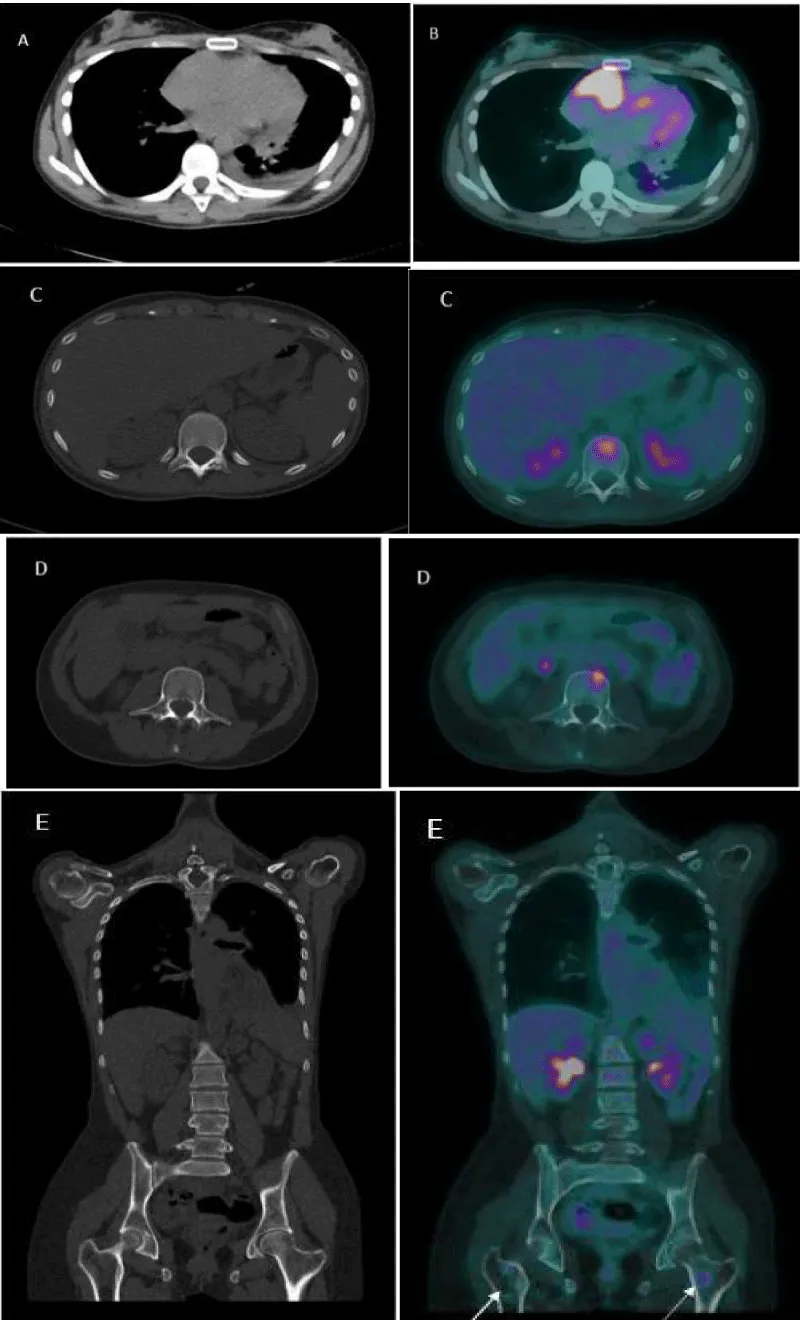

Download Image

Figure 3: An 18F-FDG-PET/CT scan. A computed tomography (CT) and B fused PET/CT: Pathological metabolic activity in the known mass in the right atrium extending along the pericardium with intensely increased FDG uptake (SUVmax) of 17.3. Moderate Pericardial effusion was noted. C, D, E (CT and fused PET/TC) showed hypermetabolic foci in the bodies of the D12 and L3 vertebrae, as well as in the proximal third of both femurs (arrows), without evidence of structural lesions on CT with SUVmax of 6.9.